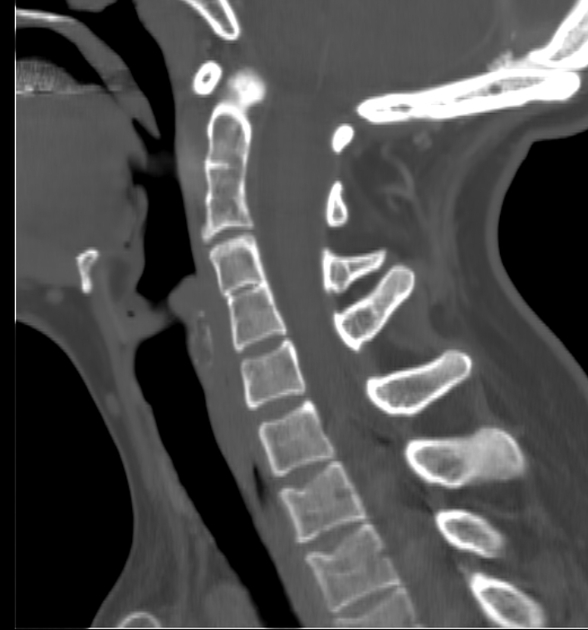

klippel fiel syndrome

incomplete segmentation of C-spine

congenital

limited mobility of neck and upper spine

diffuse idiopathic skeletal hyperostosis

calcification and ossification of anterior longitudinal ligament

can accelerate spondylosis